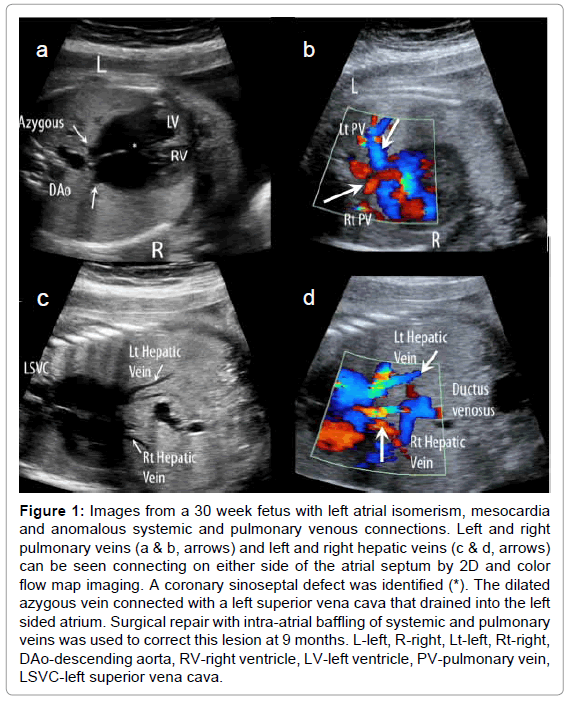

With increasing and earlier detection of fetal heart disease and serial observations, fetal echocardiography has importantly contributed to our understanding of the evolution of the spectrum of cardiovascular pathologies observed after birth [82,83]. We now know that critical outflow tract obstruction in the absence of severe atrioventricular valve insufficiency in the mid trimester fetus is often associated with the evolution of a hypoplastic ventricle and great artery ipsilateral to the obstruction [83-89]. We have also learned that functional abnormalities involving only one ventricle may also be associated with abnormal growth and progressive hypoplasia of the affected ventricle and may contribute as an etiology to such conditions as hypoplastic left heart syndrome (Figure 8) [90,91]. Ventricular outflow obstruction may progress as a primary lesion in isolation or be associated with more complex congenital heart disease such as tetralogy of Fallot. It may also evolve secondary to altered flow as is true for pulmonary outflow obstruction in Ebstein anomaly [27] and in the recipient twin in twintwin transfusion syndrome [91]. Atrioventricular and semilunar valve regurgitation and stenosis may progress and lead to more severe secondary disease including a dilated and dysfunctional ventricle, and the evolution of fetal heart failure [27-30,34] Although most structural fetal heart lesions either remain unchanged or progress, rarely there is resolution of cardiovascular pathology including progressive diminution and even closure of ventricular septal defects [90] or normalization of discrepant ventricles and great arteries detected earlier in gestation [60]. Myocardial dysfunction and arrhythmias may develop or progress in the presence or absence of structural heart disease and cardiac tumors may develop. Cardiovascular pathology may even evolve as a consequence of the abnormal intrauterine milieu. The lesions that best represents the latter is hypertrophic cardiomyopathy observed in the diabetic pregnancy which may be observed even in the late first, early second trimester [93], and we have recently found to persist even in late infancy (unpublished data). The recipient twin in twin-twin transfusion syndrome, as well, develops increased medial thickening of the systemic vascular bed and significant biventricular hypertrophy and dysfunction secondary to unique vascular placental connections between donor and recipient twins [94,95] which resolve weeks after delivery [95,96]. Knowledge of the natural history including the potential for progression of fetal heart disease has become a critical part of the counseling of affected pregnancies, has improved counseling with respect to recurrence of pathology in subsequent pregnancies, and has led to the desire to develop interventional strategies that improve the ultimate outcome of affected pregnancies.

clinical-experimental-cardiology-critical-aortic

Figure 8: Images from a 21 week fetus with critical aortic stenosis. a) At this stage in addition to a thickened and hypoplastic aortic valve, the left ventricle (LV) was found to be severely dilated and akinetic. There was b) left to right atrial flow and c) retrograde aortic arch flow in keeping with high left heart filling pressures and severely reduced left ventricular output, respectively. With redistribution of blood flow to the right heart and decreased filling of the left ventricle, there was progressive left heart hypoplasia such that by 35 weeks the fetus had findings consistent with hypoplastic left heart syndrome. LA-left atrium, RV-right ventricle, RA-right atrium, L-left, R-right, DAo-descending aorta.